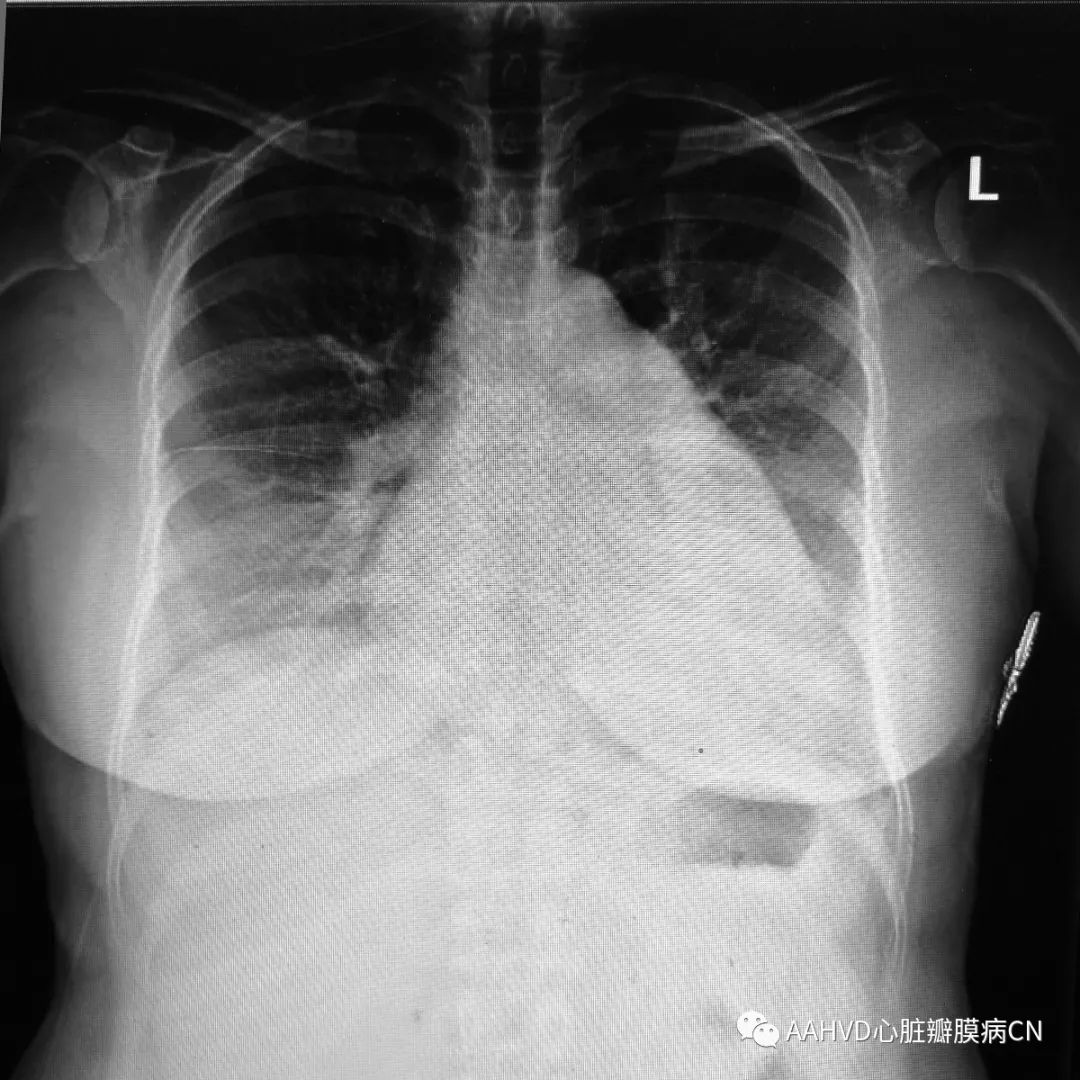

术前胸片

640_2